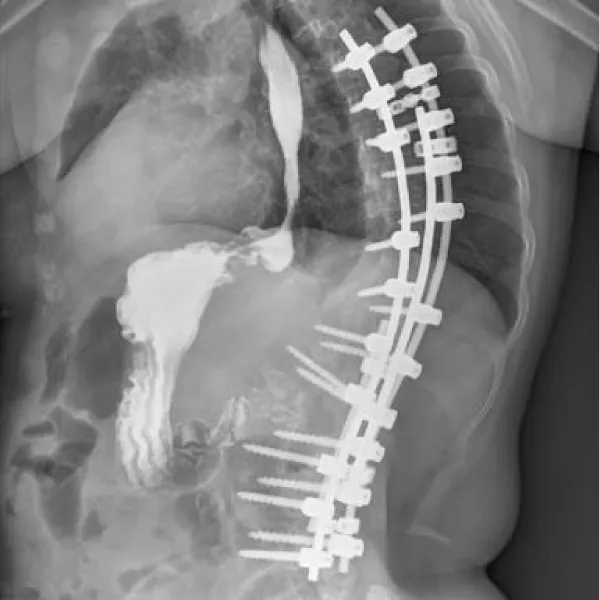

The patient had a history of spinal correction surgery for scoliosis five years ago, during which her SIT was identified. Our CT exam and gastrogram proved her history, with a hernia sac measuring 35*48 mm (Figures 2-4). All routine laboratory tests were within normal limits.

Download Image

Figure 3: Lateral view of the gastrogram before surgery.